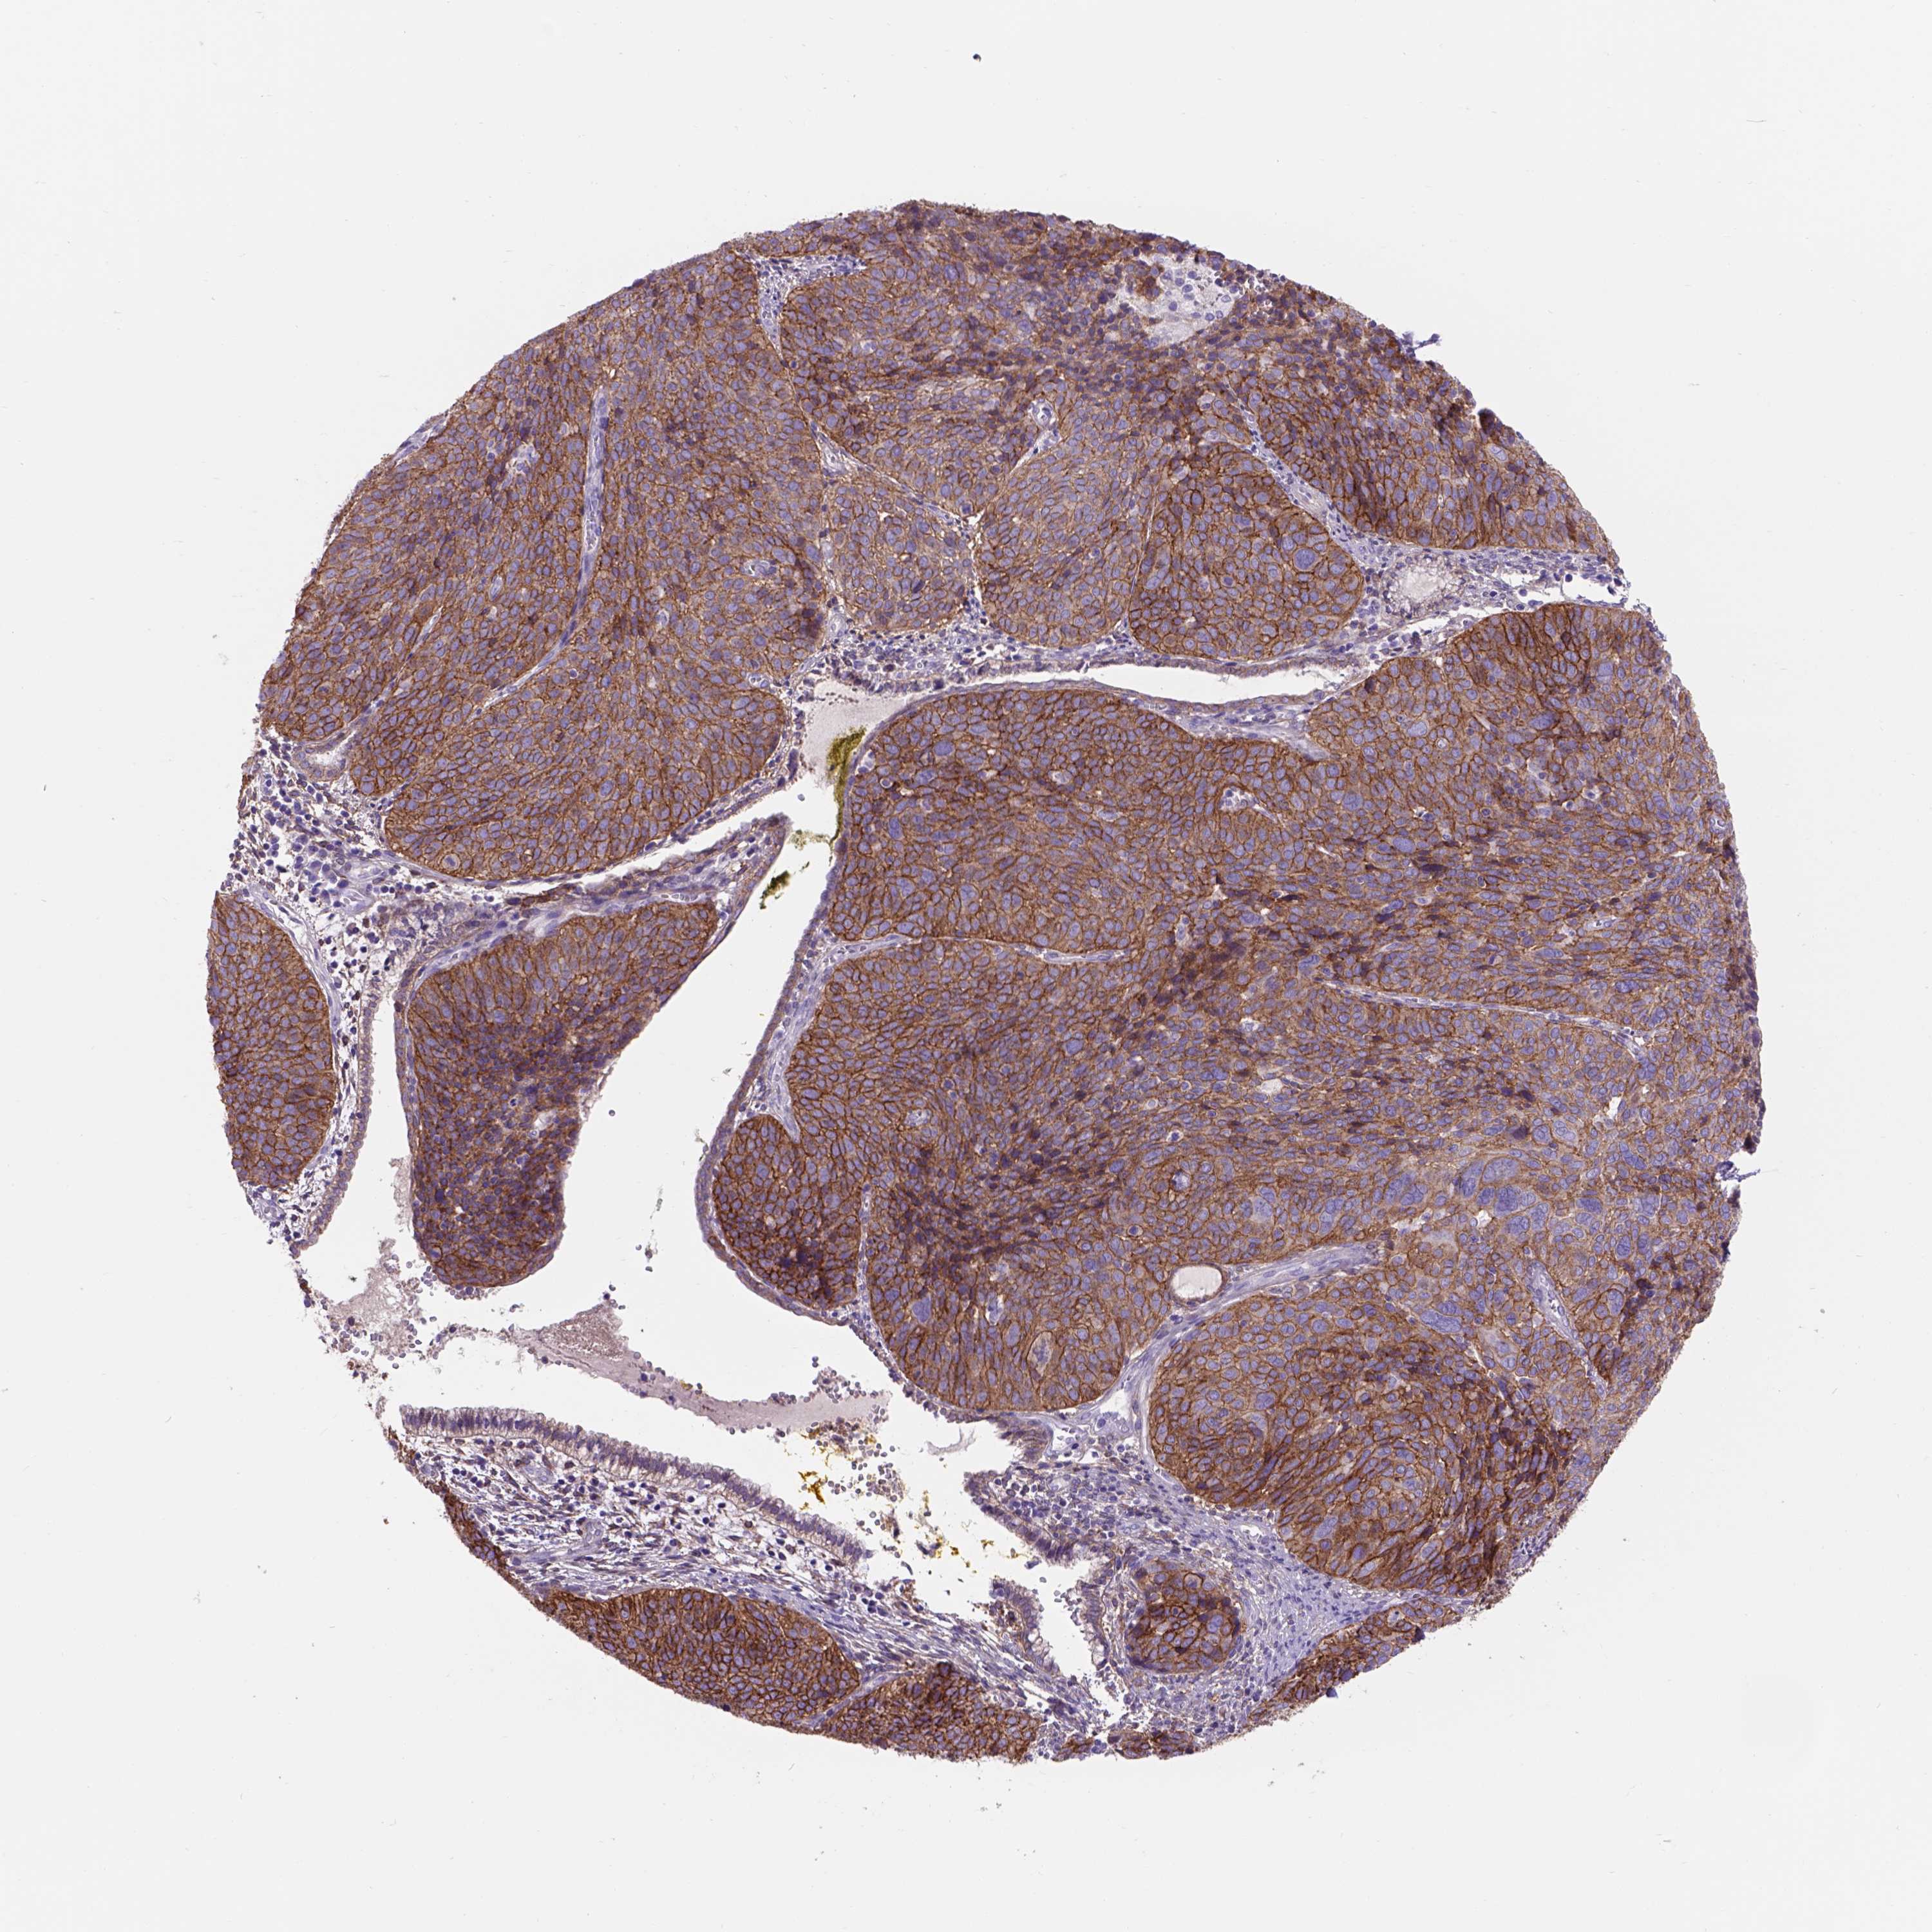

CERVICAL CANCER - Protein expressioni

A mouse-over function shows sample information and annotation data. Click on an image to view it in a full screen mode. Samples can be filtered based on level of antibody staining by selecting one or several of the following categories: high, medium, low and not detected. The assay and annotation is described here.

Note that samples used for immunohistochemistry by the Human Protein Atlas do not correspond to samples in the TCGA dataset.

Antibody stainingi

Antibody staining in the annotated cell types in the current human tissue is reported as not detected, low, medium, or high, based on conventional immunohistochemistry profiling in selected tissues. This score is based on the combination of the staining intensity and fraction of stained cells.

Each image is clickable and will lead to virtual microscopy that enables deeper exploration of all samples and also displays staining intensity scores, fraction scores and subcellular localization as well as patient and tissue information for each sample.

HPA001200

HPA018530

CAB000035

CAB068186

CAB073534

CAB080313

CAB080314

CAB080473

CAB080475

CAB080506

CAB080507

CAB080509

CAB080510

CAB080511

Staining

High

Medium

Low

Not detected

Intensity

Strong

Moderate

Weak

Negative

Quantity

>75%

75%-25%

<25%

None

Location

Nuclear

Cytoplasmic/membranous

Cytoplasmic/membranous,nuclear

Adenocarcinoma, NOS

Squamous cell carcinoma, NOS